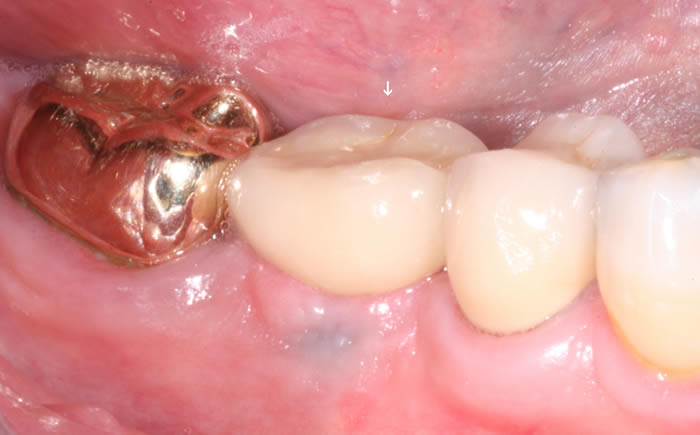

More back teeth replaced by dental implants

Case Three (2 images)